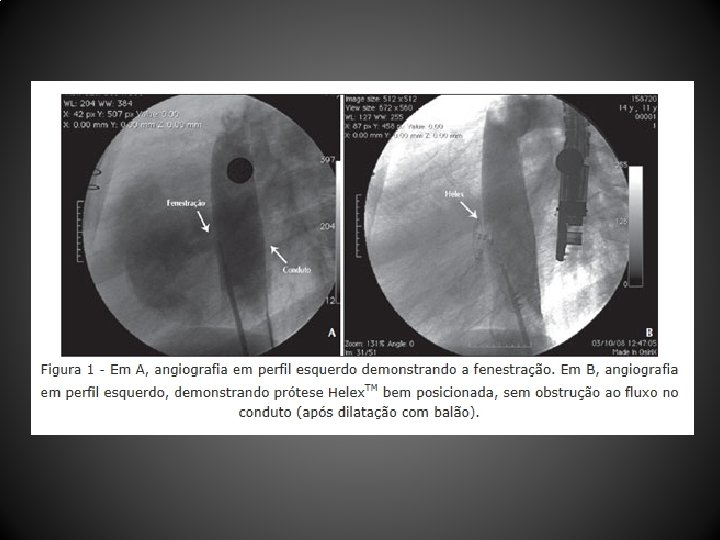

Métodos • Estudo descritivo longitudinal, observacional, retrospectivo, de uma • • coorte não-consecutiva de pacientes O procedimento foi realizado sob anestesia geral com a ajuda de ecocardiograma transesofágico O teste de oclusão da fenestração com cateter Bermann angiográfico foi realizado antes da intervenção No caso de elevação da pressão venosa do circuito de Fontan de 4 -5 mm. Hg para valores superiores a 18 -20 mm. Hg, acompanhada de redução > 20% do débito cardíaco (avaliado pelo método de Fick e da diferença arteriovenosa de oxigênio) e > 20% da pressão arterial sistêmica, o procedimento era contraindicado Diferentes técnicas e dispositivos foram empregados para a oclusão da fenestração

Resultados • Entre abril de 2004 e dezembro de 2010, 12 pacientes (média de idade, 103, 1 + 88, 6 meses; peso, 29, 9 + 12, 7 kg) submetidos a CF (10 tubos extracardíacos, 2 túneis intra-atriais) foram tratados 44, 1 + 26, 7 meses após a CF • Um paciente não tolerou o teste de oclusão com o balão, sendo contraindicado o procedimento • As próteses utilizadas foram: Helex. TM (4 pacientes), Amplatzer. TM (2 pacientes), Cardia Atriasept. TM (2 pacientes), Figulla. TM (1 paciente), Cera. TM (1 paciente), e 1 stent coberto Cheatham-Platinum. TM • Após a oclusão da fenestração, a saturação de oxigênio aumentou significativamente (82, 1 + 6, 5% para 95, 2 + 3, 2%), sem aumento significativo da pressão venosa central (12, 4 + 2, 6 mm. Hg para 14, 5 + 2, 3 mm. Hg) nem queda do débito cardíaco • Após o procedimento foi observado shunt residual imediato em 5 pacientes, que desapareceu antes da alta